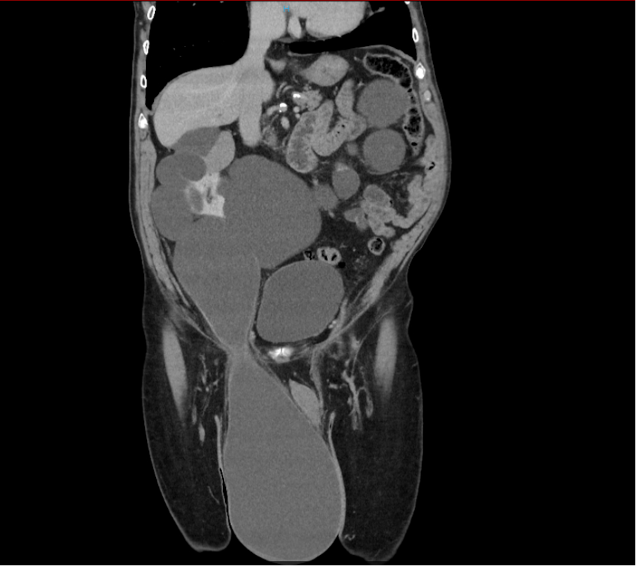

Einleitung: Die adulte Hydrozele stellt eine gutartige Vergrößerung des Skrotums dar, die bei ungefähr 60/100.000 Männern älter als 18 Jahren beobachtet werden kann. Hierbei handelt es sich um eine Ansammlung von Flüssigkeit im Cavum serosum testis. Die Differenzialdiagnosen umfassen unter anderem extratestikuläre Pathologien, darunter hernierte abdominelle oder retroperitoneale Strukturen.

Die Herniation einer Nierenzyste in das Skrotum stellt eine außergewöhnliche Rarität dar, die im vorliegenden Casus initial als Hydrozele testis fehlgedeutet wurde.

Dieser Fall unterstreicht die Bedeutung einer sorgfältigen differenzialdiagnostischen Abklärung skrotaler Raumforderungen, insbesondere bei atypischer Klinik oder ungewöhnlicher Bildgebung.